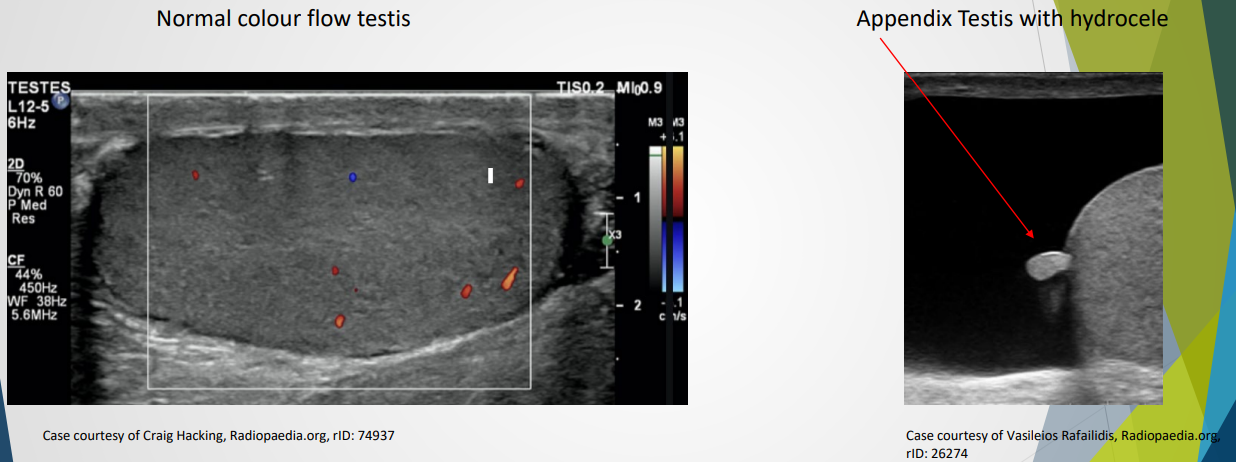

Testes:

Medium homogeneous appearance.

Tunica albuginea visible as a thin echogenic line surroudning the testes

Tunica invaginates to form a linear ehcogenic mediastinum testis

Rete testis may appear as a hypoechoic region near mediastinum and easily visible if dilated

Appnedix testis can be seen if combined with a hydrocele

Appears echogenic on ultrasound; color Doppler shows testicular artery and plexus.